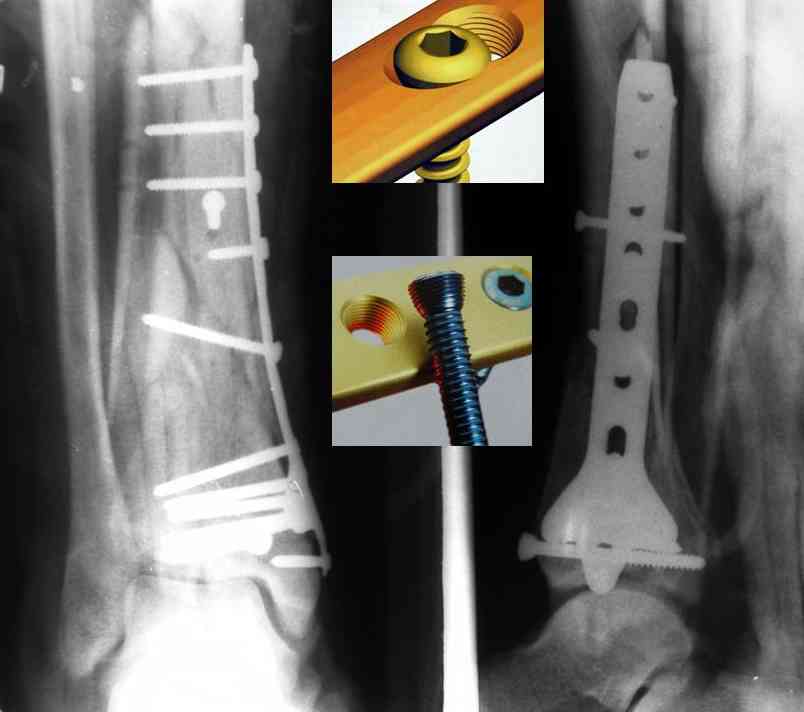

На рентгенограммах типичный перелом пилона по типу С-3. есть опыт до 100 открытых опреаций у нас в клинике. 20 примерно в год. Принцип один -все внутрисуставные переломы нуждаются в открытой репозиции и внутренней стабильной фиксации. При поступлении КТ не надо, так как получается только нагромождение костей. Истинной картины нет. Главное восстановить длину малоберцовой кости - это ключ к успеху. При поступлении меньше всего надо думать о сосудистых расстройствах, т.к. сама операция и репозиция даже сначала частичная даёт улучшение сосудитых нарушений. Причём очень быстро. Операция в 2этапа. При поступлении доступ позади наружной лодыжки, причём обязательно. После этого репозиция малоберцовой кости и фиксация пластиной 1/3 трубки под винт 3,5. Дренаж и любой аппарат наружной фиксации. Затем после спадения отёка на 5-7-10 день аппрат снимается и дугообразный разрез спереди от медиальной лодыжки 10-12 см. Главной чтобы расстояние между 1 и вторым разрезом было не меньше 7-8 см. Тогда не будет некрозов лоскутов. Таранная кость используется как матрица на неё укладываются отломки и фиксируются пицами. Ренг-контроль. Отломки лежат все отдельно, но ничего не высыпется. При переломах С-3 всегда нужна костная пластика (из крыла). Фиксация пластиной лист клевера простой или LCP. Гипс не нужен. Дренаж до 48 часов. Операция длится 3-4 часа обязательно без жгута. Посылаю примерно такой же случай.

Отправитель: Дрягин В. 04 Январь 2007, 09:01

Послала ещё два снимка, если не пройдут, пошлю ещё. Дрягин. Если есть вопросы, готов ответить.

Кстати, при переломах переднего края по классификации АО В-3 при переломах пилона пластина укладывается по передней поверхности. Она достаточно тонкая и эластичная, не надо этого бояться. Посылаю три снимка.